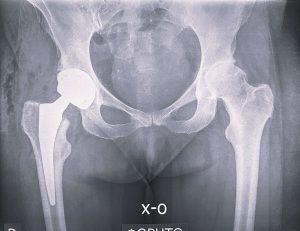

Ακτινολογική εικόνα της λεκάνης και των ισχίων. Στο δεξί ισχίο διαπιστώνεται βαριά εκφυλιστική οστεοαρθρίτιδα η οποία συνοδεύεται από έντονη συμπτωματολογία πόνου καθώς και κινητική αναπηρία.